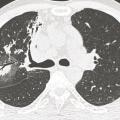

Aspergillose pulmonaire invasive

ASPERGILLOSE PULMONAIRE

Image